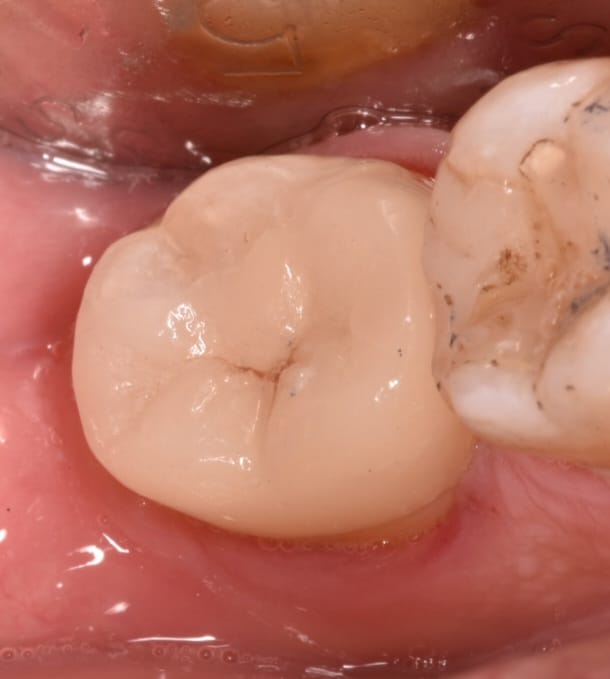

Immediate result direct view

Immediate result